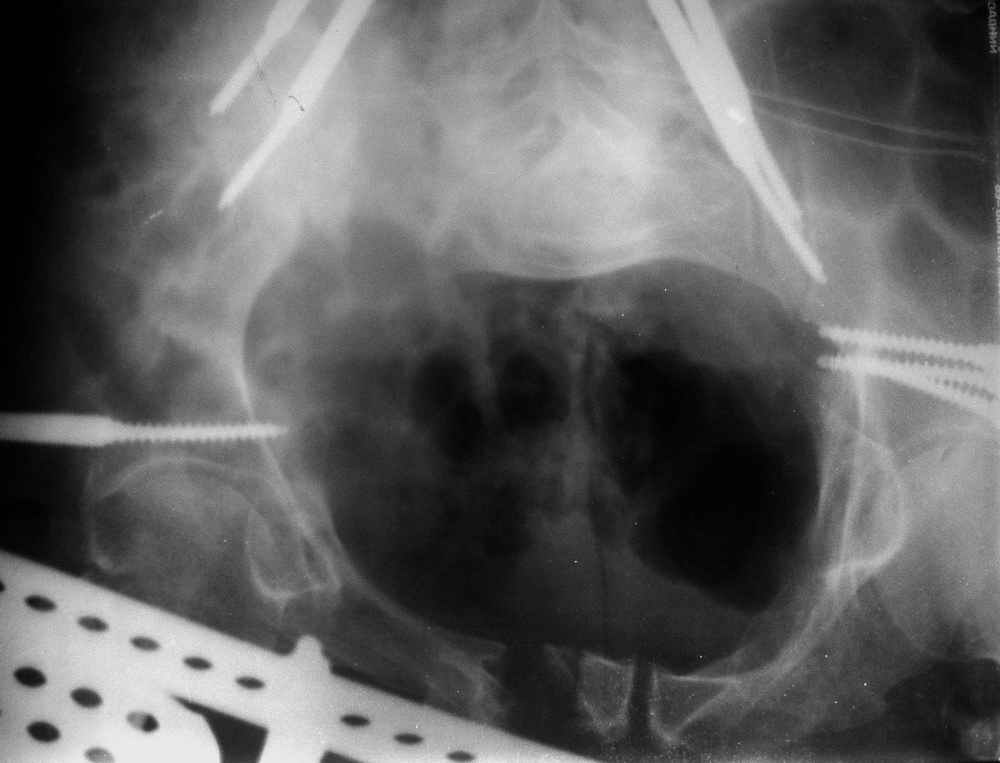

отеотомия передних и задних отделов, дистракция аппаратом

окончательная фиксация